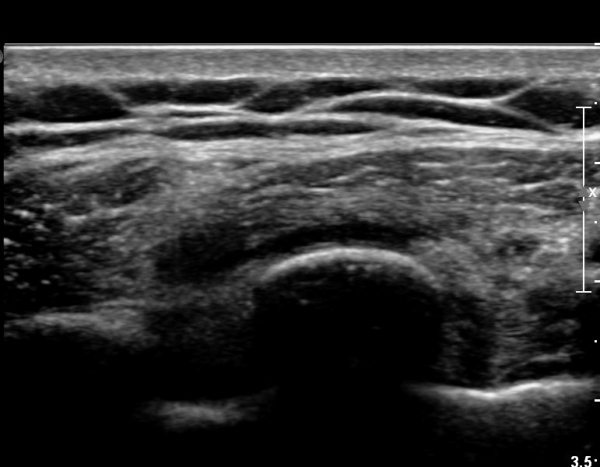

8¹øÂ° °¥ºñ»À Á¾´Ü¸é°Ë»ç»ó °¥ºñ»À Ç¥ÃþÀ¸·Î Àú¿¡ÄÚ ºÎÁ¾°ú °¥ºñ»À Ç¥Ãþ¿¡ ÀÖ´Â

±Ù¼¶À¯µéÀÌ Ç¥ÃþÀ¸·Î ¹Ð·ÁÀÖ´Â °ÍÀÌ °üÂûµÇ°í(»çÁø 1, 2) °¥ºñ»À ÇÇÁú°ñ ¿¬¼Ó¼º

´ÜÀýÀÌ ÀǽɵȴÙ(»çÁø 2).